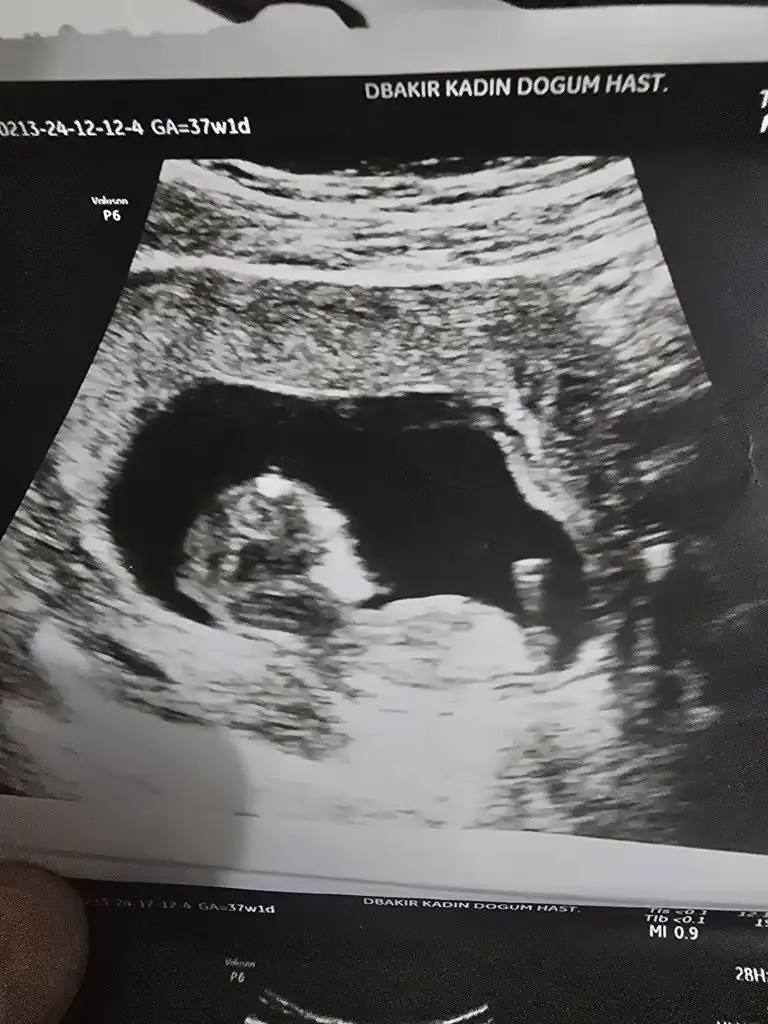

Bize de bakabilir misiniz bugün ki ultrasyondan 12+2

Fotoğraf yokBize de bakabilir misiniz bugün ki ultrasyondan 12+2

kız olabilir kese yuvarlak